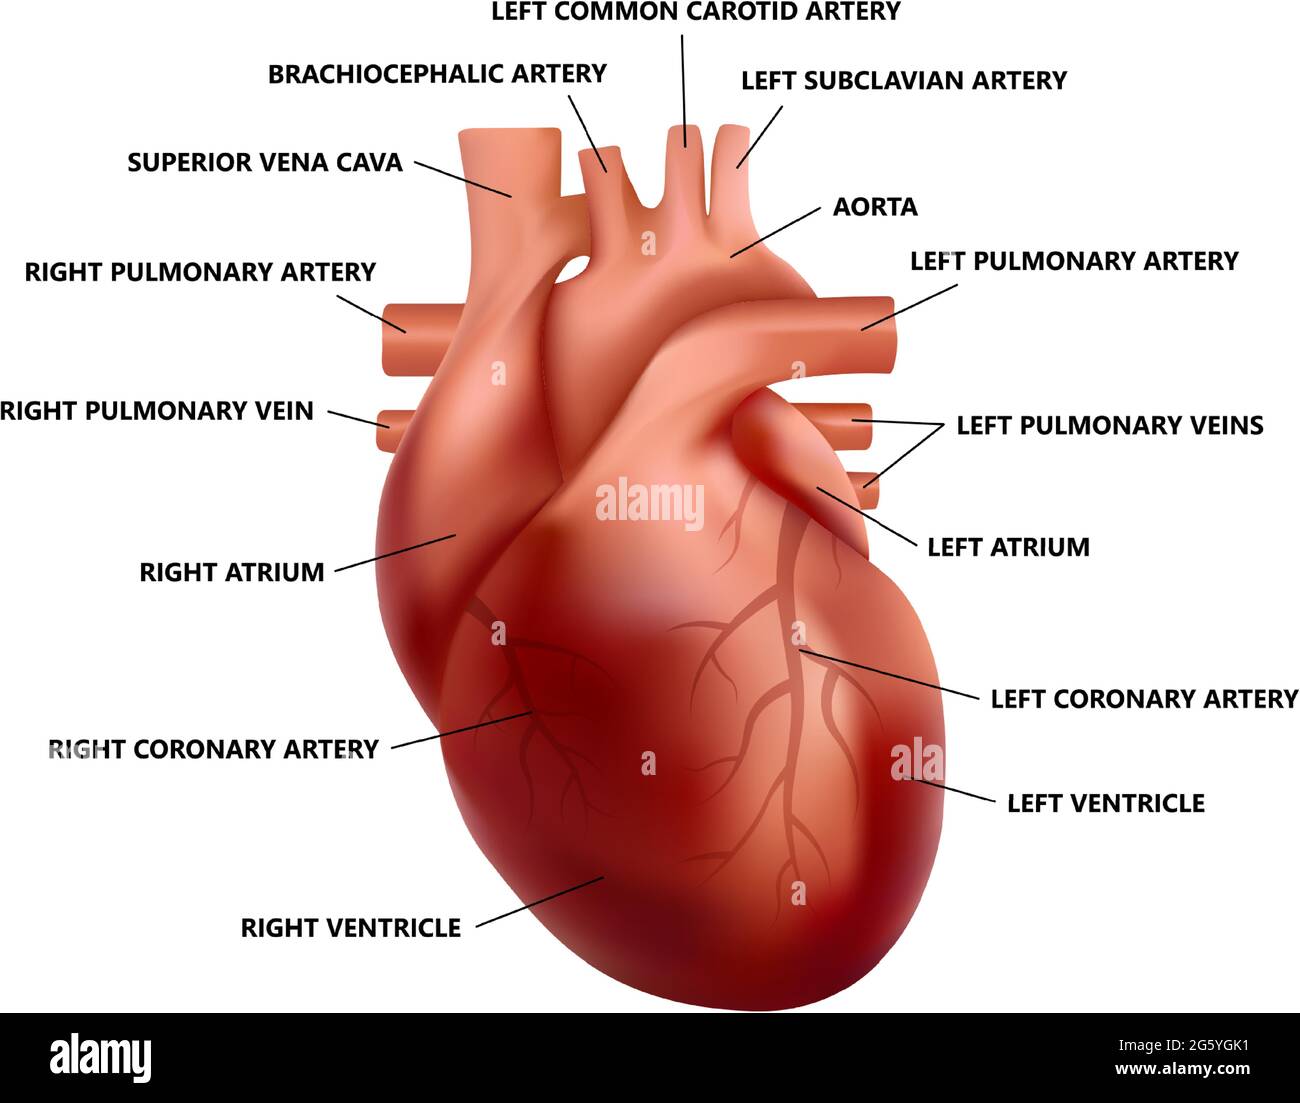

Realistic heart anatomy with descriptions. Diagram of human heart illustration. Stock Vectorhttps://www.alamy.com/image-license-details/?v=1https://www.alamy.com/realistic-heart-anatomy-with-descriptions-diagram-of-human-heart-illustration-image433938261.html

Realistic heart anatomy with descriptions. Diagram of human heart illustration. Stock Vectorhttps://www.alamy.com/image-license-details/?v=1https://www.alamy.com/realistic-heart-anatomy-with-descriptions-diagram-of-human-heart-illustration-image433938261.htmlRF2G5YGK1–Realistic heart anatomy with descriptions. Diagram of human heart illustration.